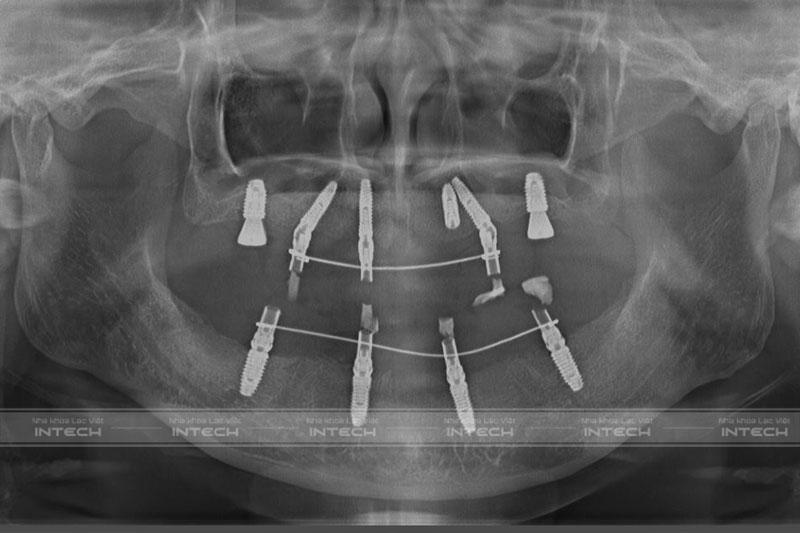

Dưới đây là hình ảnh phim chụp X-quang của cô Thủy sau khi cấy ghép Implant All On 6 hàm trên và All On 4 hàm dưới.

Hình ảnh phim chụp X-quang sau khi cấy Implant của cô ThủyHình ảnh phim chụp X-quang sau khi cấy Implant của cô Thủy

Có thể thấy rằng các trụ Implant đều được phân bố đều, giúp nâng đỡ toàn bộ răng trên cung hàm. Với công nghệ Safe Tech thì việc nhổ răng và cấy Implant tức thì là điều rất dễ dàng. Ngay sau khi cấy ghép Implant, bệnh nhân sẽ được lắp hàm tạm để có thể ăn nhai thoải mái và đảm bảo thẩm mỹ.